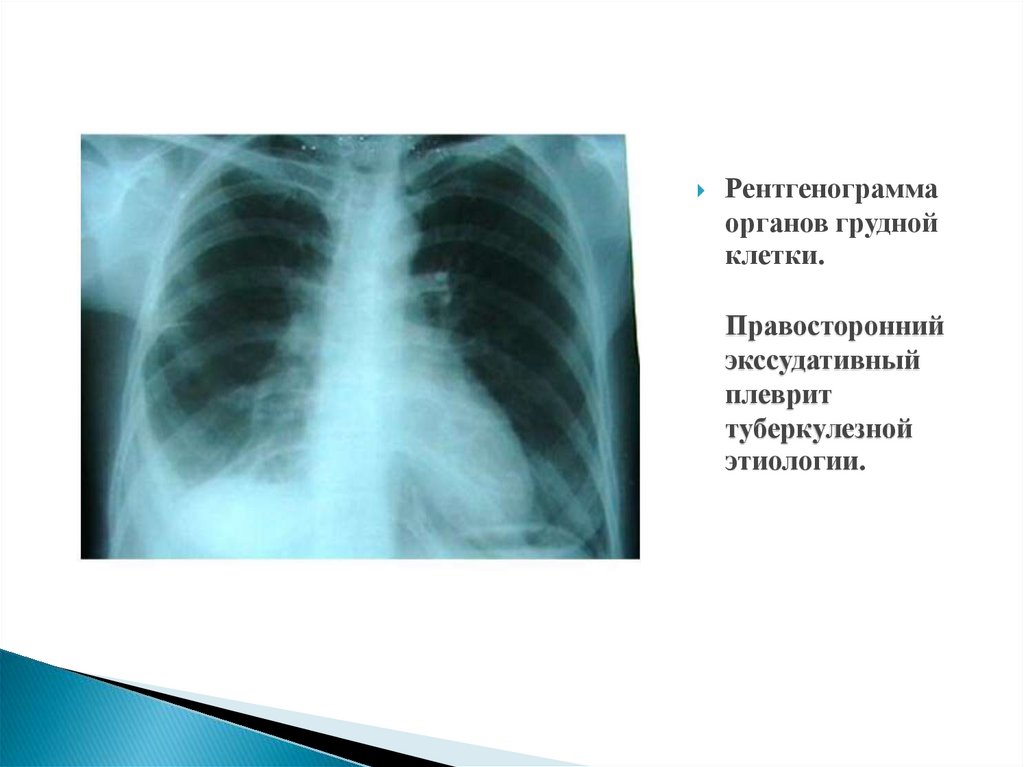

Рентгенограмма органов грудной клетки. Правосторонний экссудативный плеврит туберкулезной этиологии.

12. Рентгенограмма органов грудной клетки. Правосторонний экссудативный плеврит туберкулезной этиологии.

13.

Рентгенограмма

органов грудной

клетки.

Правосторонний

экссудативный

плеврит

туберкулезной

этиологии.

14.